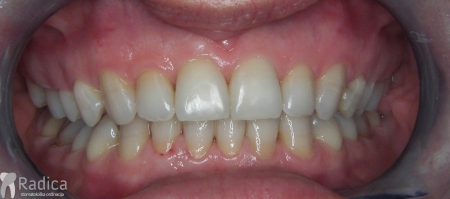

Slučaj 1: ispravljanje otvorenog zagriza i kompresije Invisalign full terapijom

Slučaj 2: ispravljanje kompresije Invisalign full terapijom- u ovom slučaju je izvađen jedan donji sjekutić

Slučaj 3: ispravljanje kompresije Invisalign full terapijom

Slučaj 4: ispravljanje kompresije Invisalign full terapijom

Slučaj 5: ispravljanje kompresije i križnog zagriza Invisalign full terapijom

Slučaj 6: ispravljanje kompresije i dubokog zagriza Invisalign full terapijom

Slučaj 7: ortodontska predprotetska terapija Invisalign full